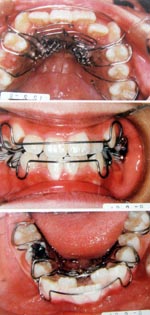

小さい顎には装置を使用します。1日10時間程度、自宅で装置を使い、歯を抜かずに本来の位置まで顎を成長させる治療です。

矯正後

自然に歯が並びます。また、空間ができて、いびき、無呼吸症候群が解消します(個人差があります)

症状の改善には個人差があります。